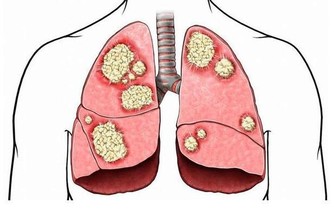

疾病一些疾病也會對導致牙齒顏色變化,

比如新陳代謝類疾病、缺鈣、肝病、佝僂病、飲食紊亂症、乳糜瀉等。